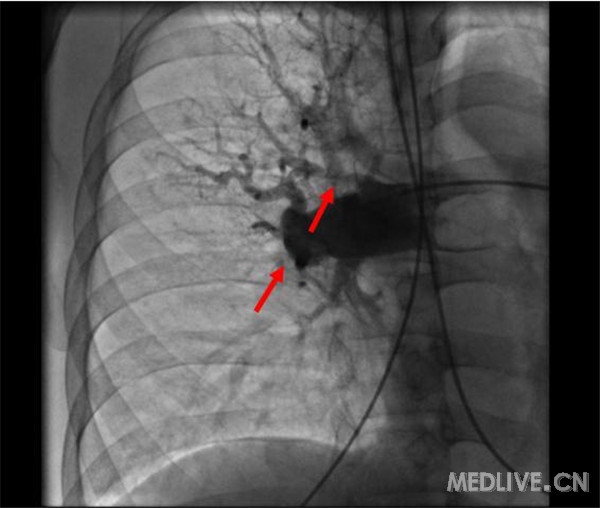

肺动脉造影示:左、右肺动脉扩张,管壁僵硬,右肺下叶动脉开口闭塞,远端血流灌注缺失;右肺上叶前段及中叶分支可见多发狭窄,远端血流灌注呈节段性减低(图2);左肺下叶内前基底段开口重度狭窄,余基底段动脉亚段以下分支可见多发狭窄性病变,远端血流灌注明显减低(图3)。